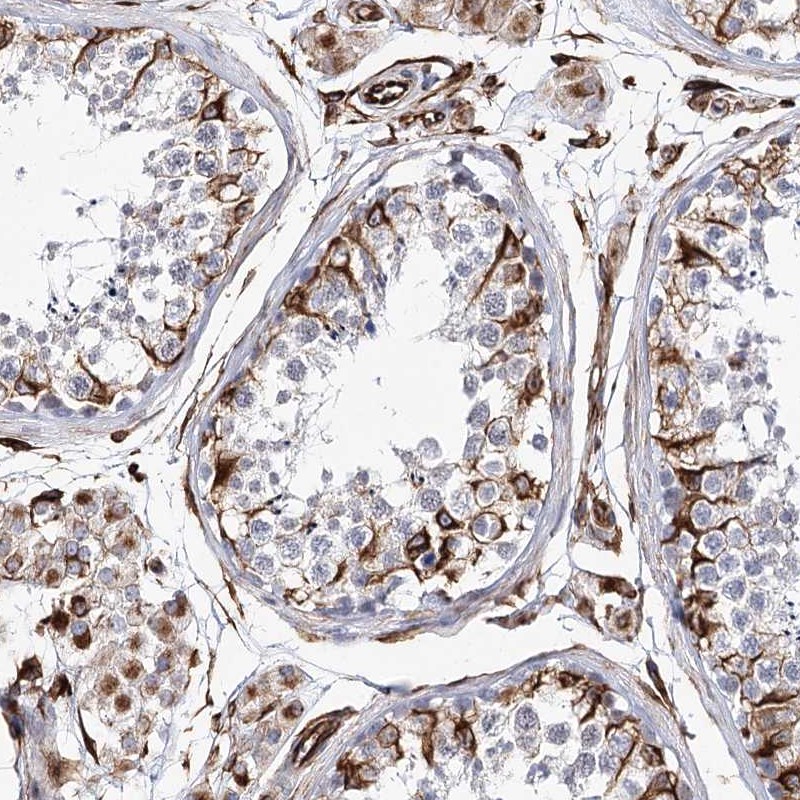

Immunohistochemical staining of human testis shows strong cytoplasmic positivity in Sertoli and Leydig cells.